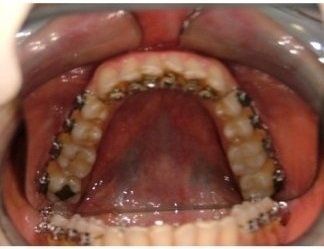

L'idea innovativa di applicare delle maniglie (brackets) sul lato interno dei denti, rivolto alla lingua anziché sul lato esterno rivolto al labbro ed esposto al sorriso, ha fatto sì che questa tecnica venisse denominata “linguale".